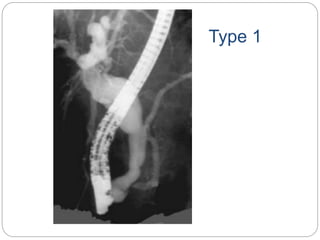

TYPES (Todani ‘s )

 Type I- Cystic (51 %) or fusiform

(10.6%)

 TypeII- Diverticulum

 Type IlI- Choledochocele of

intraduodenal common bile duct

 Type IV- Extra- and intrahepatic cysts

(28.5%)

 Type V- Intrahepatic dilatations (4.6%)

Type 1